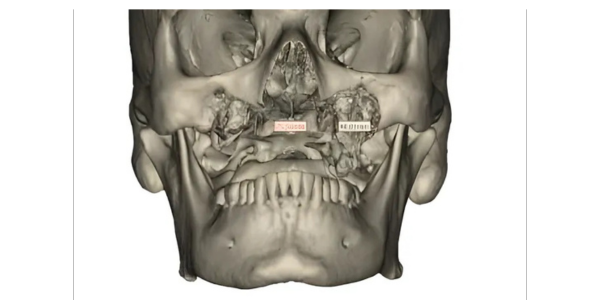

Ms. Mr Manik Kale, a 47-year-old male,

residing at Pune had to undergo

Maxillectomy due to Mucormycosis leaving

a large defect on his maxilla.

Surgeon after severe brainstorming concluded the need of PSI (Patient specific implant to correct the defected part of the patient)